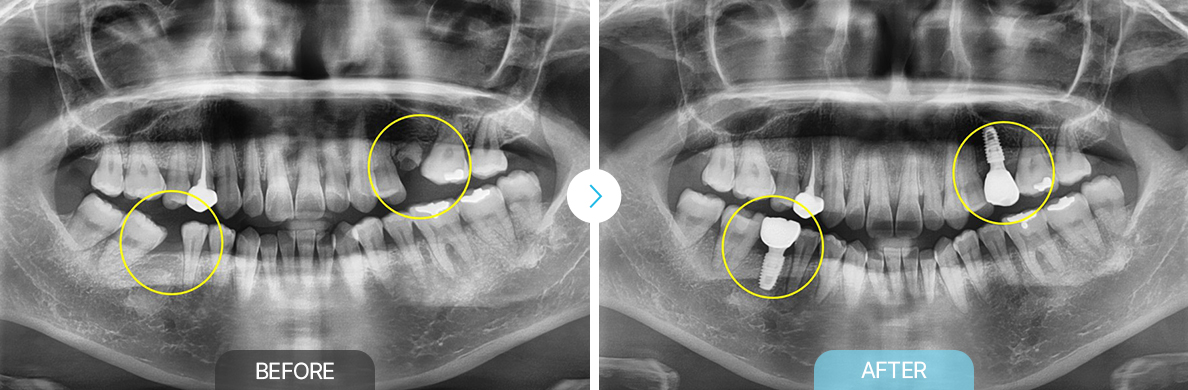

치료전후사진

보철교정

부천상동 보철교정, 상동 보철교정, 부천치과 부천연세퍼스트치과 보철교정, 부천상동 교정, 보철교정 상동